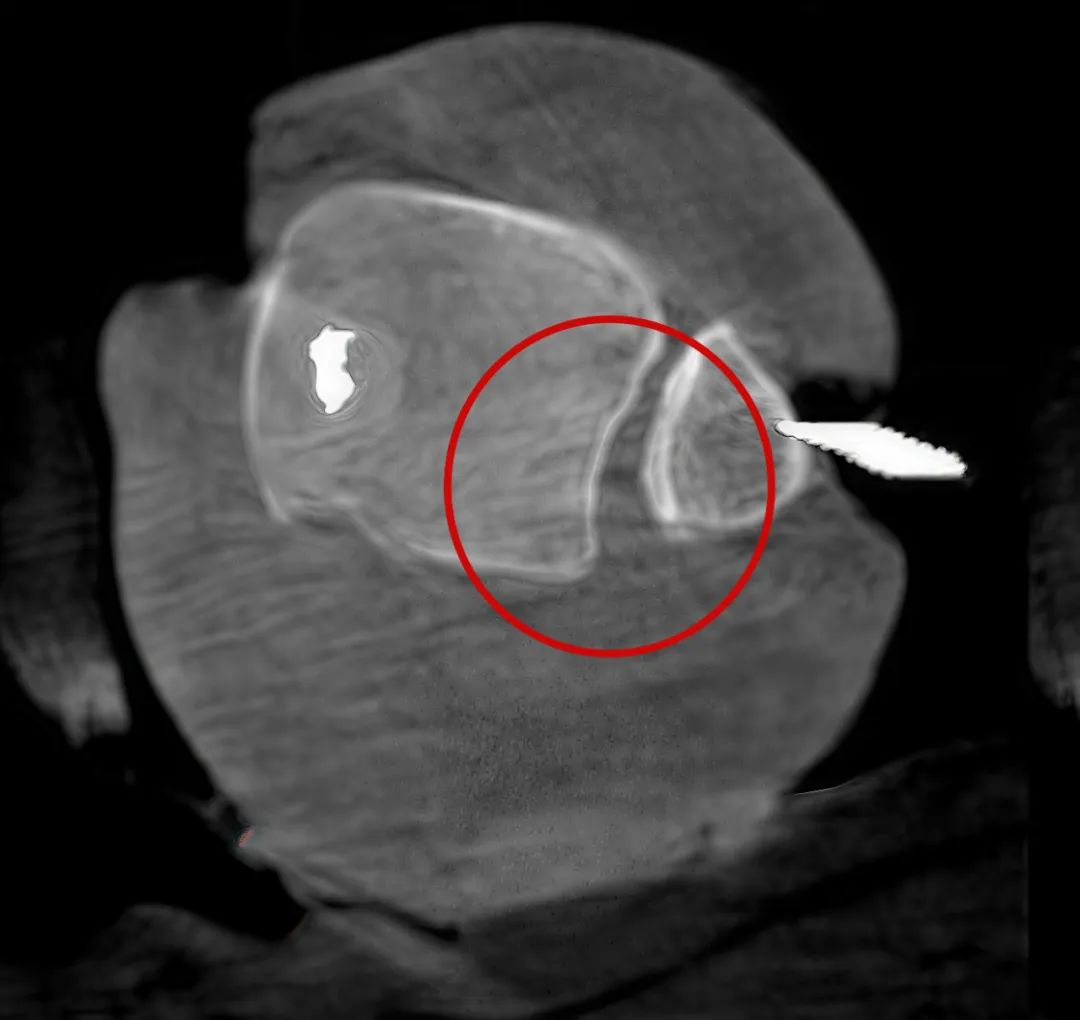

三維“類CT”影像

病例1:右側股骨遠端骨骺骨病(13歲)

二維影像看不到病灶點

三維切面影像可以看出病灶點